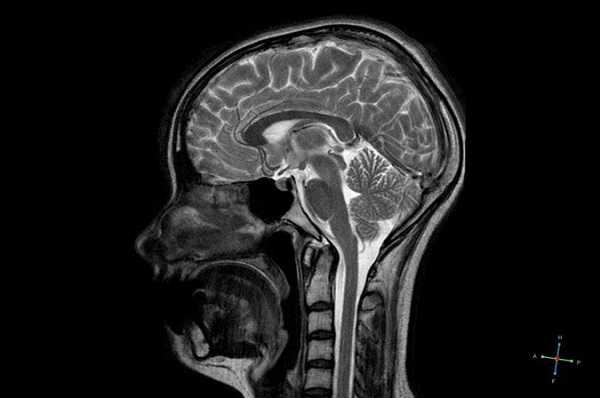

МРТ гипофиза при краниофарингиоме: сканы в разных проекциях

Магнитно-резонансная томография - один из высокоинформативных способов инструментальной диагностики. Исследование показывает мельчайшие изменения в структуре органов, предположительный характер патологии, взаимоотношение с близлежащими структурами. Скульптурирование многоплоскостных изображений во время МР-сканирования подразумевает использование принципа ядерно-магнитного резонанса, но не рентгеновских лучей. Атомы водорода в клетках воды, попав в поле, генерируемое аппаратом, начинают перестраиваться, при обретении привычного положения выделяется определенное количество энергии, которое фиксируют датчики, а обрабатывает компьютерная программа. Какого-либо вредоносного воздействия на организм во время диагностической процедуры нет, при условии отсутствия в теле металлических составляющих. Врач получает возможность рассматривать патологический очаг в любой плоскости, что невозможно при обычной рентгенографии или КТ.